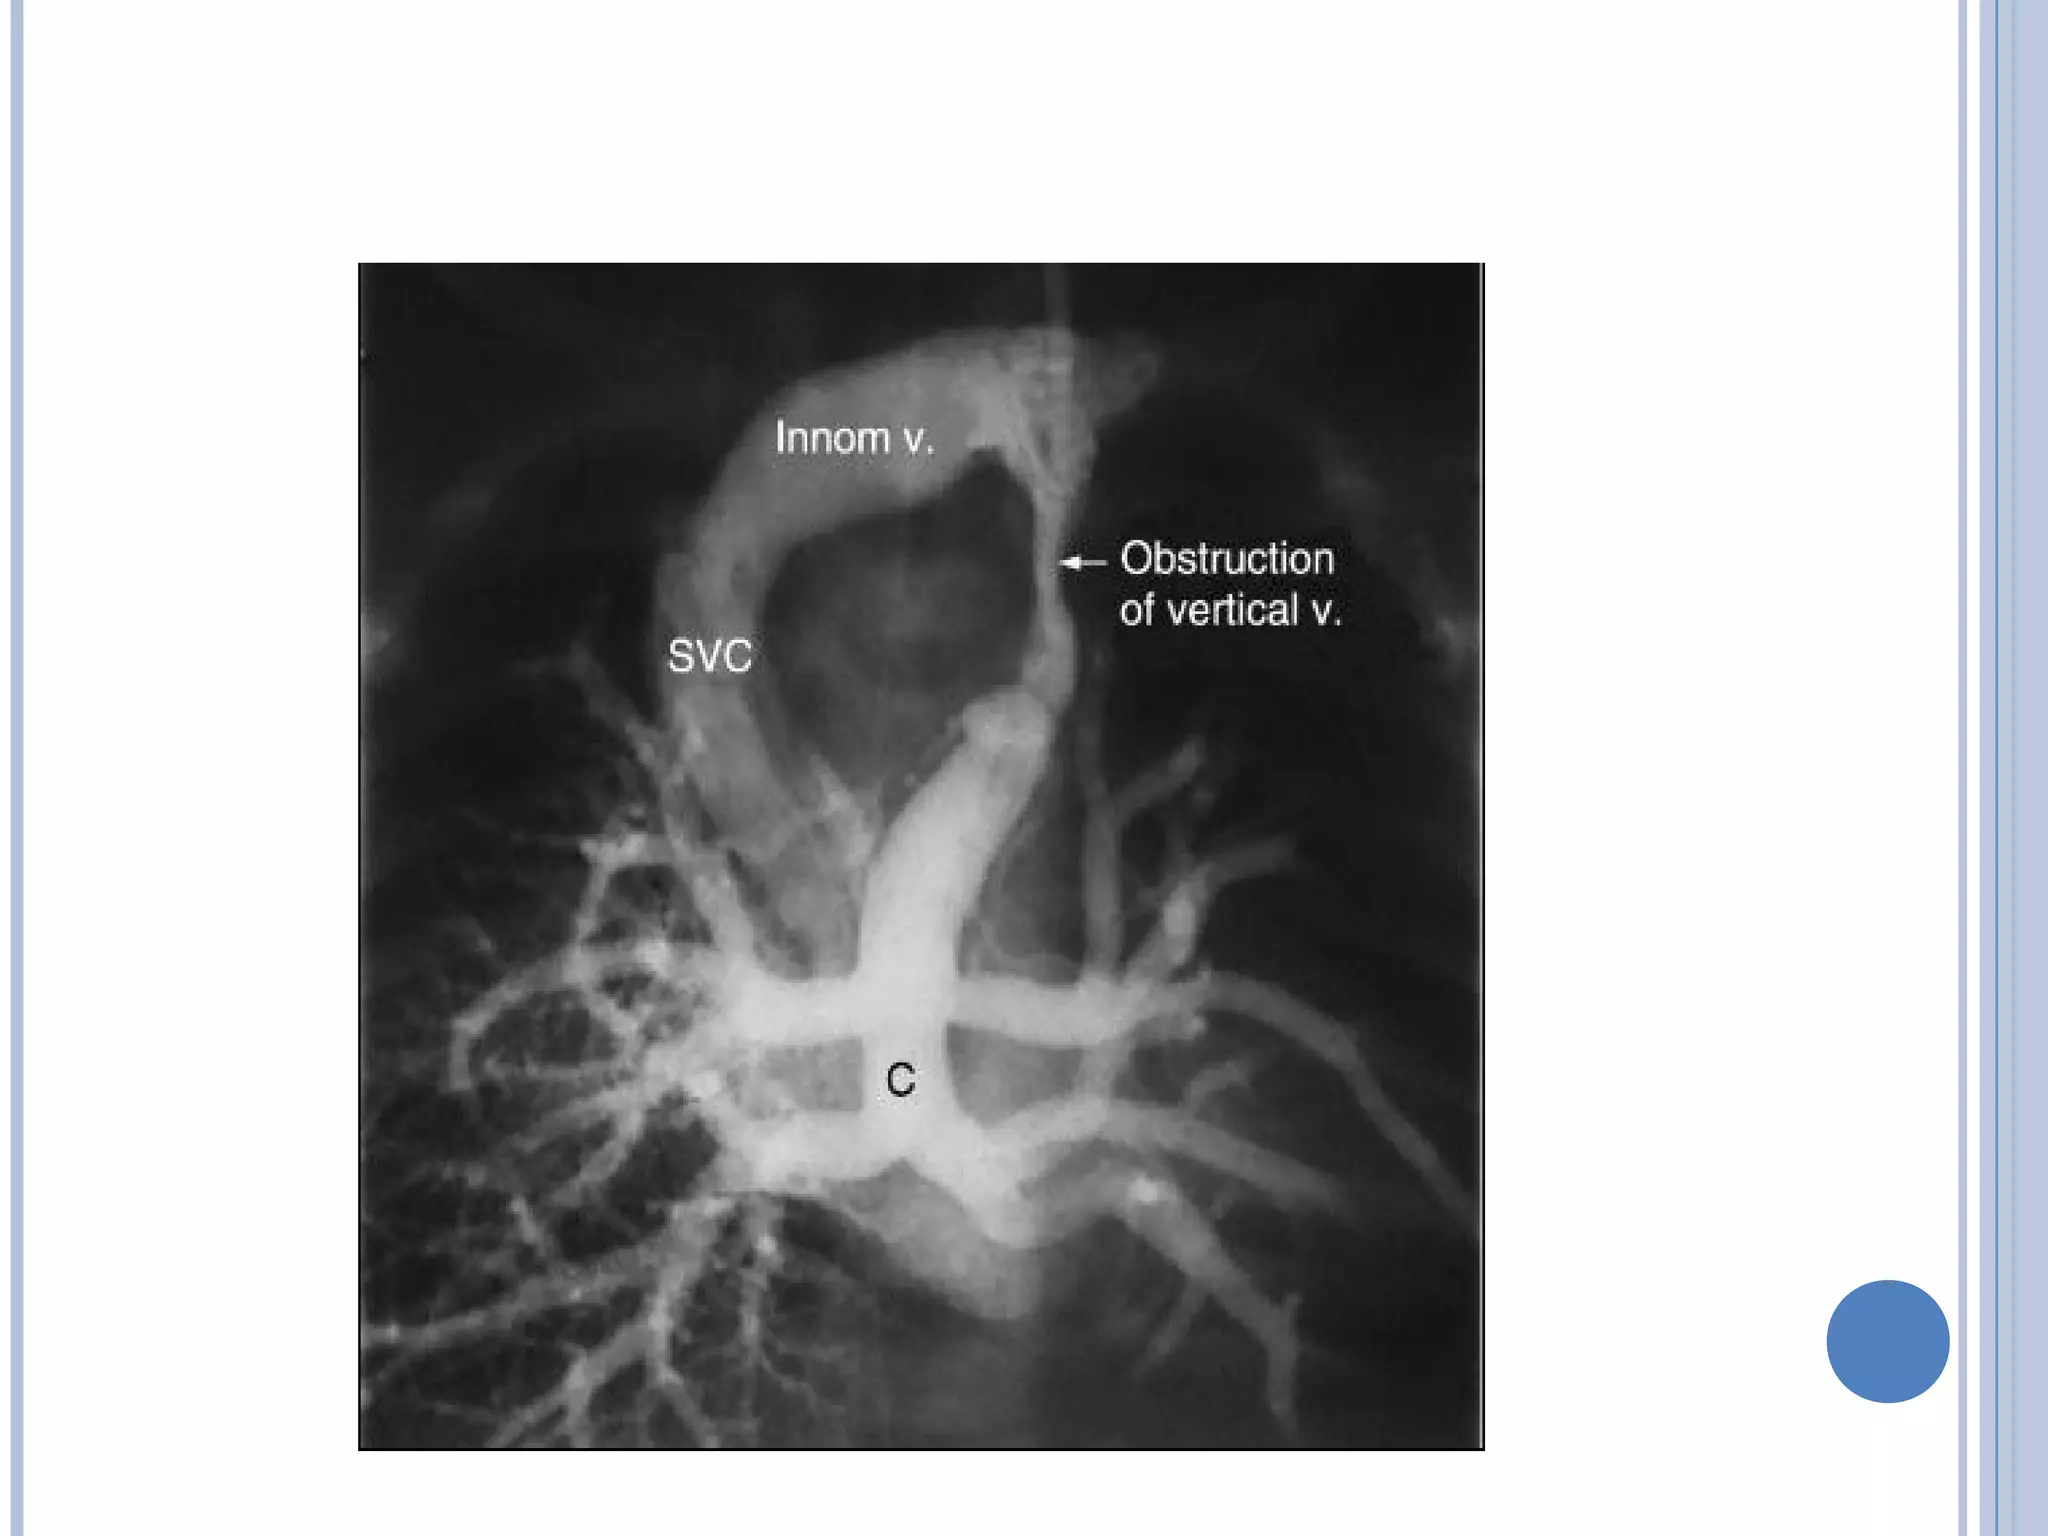

 Obstruction in the Anomalous Venous Channel

 Intrinsic narrowing in the walls of the anomalous vessels or

Extrinsic pressure results in narrowing of venous structure .

For example, when the vertical vein in TAPVC to the

innominate vein passes between the left main pulmonary

artery and left main bronchus.